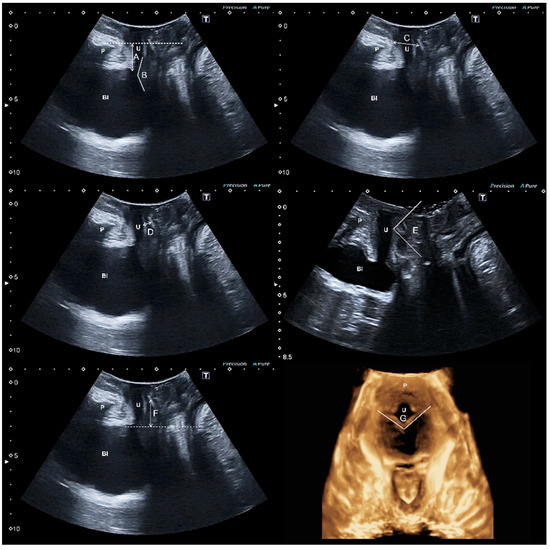

2.3. Ultrasound Assessment